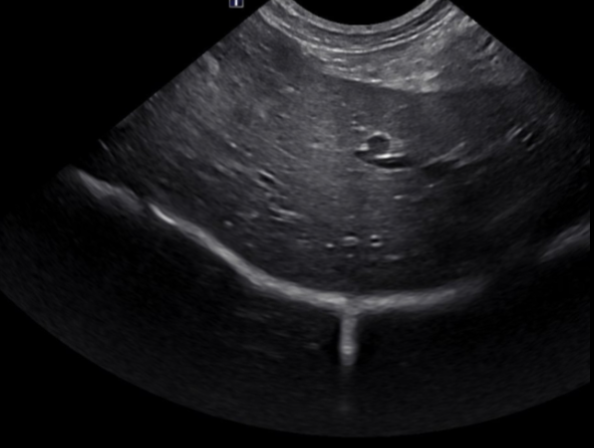

Hyperechoic

(very bright) strong reflection

ex. bone, fat, calcifications, scar tissue

Hypoechoic

(darker): weaker reflection

ex. many soft tissues

Anechoic

(black): no echoes

Example: fluid (like cysts or blood vessels)